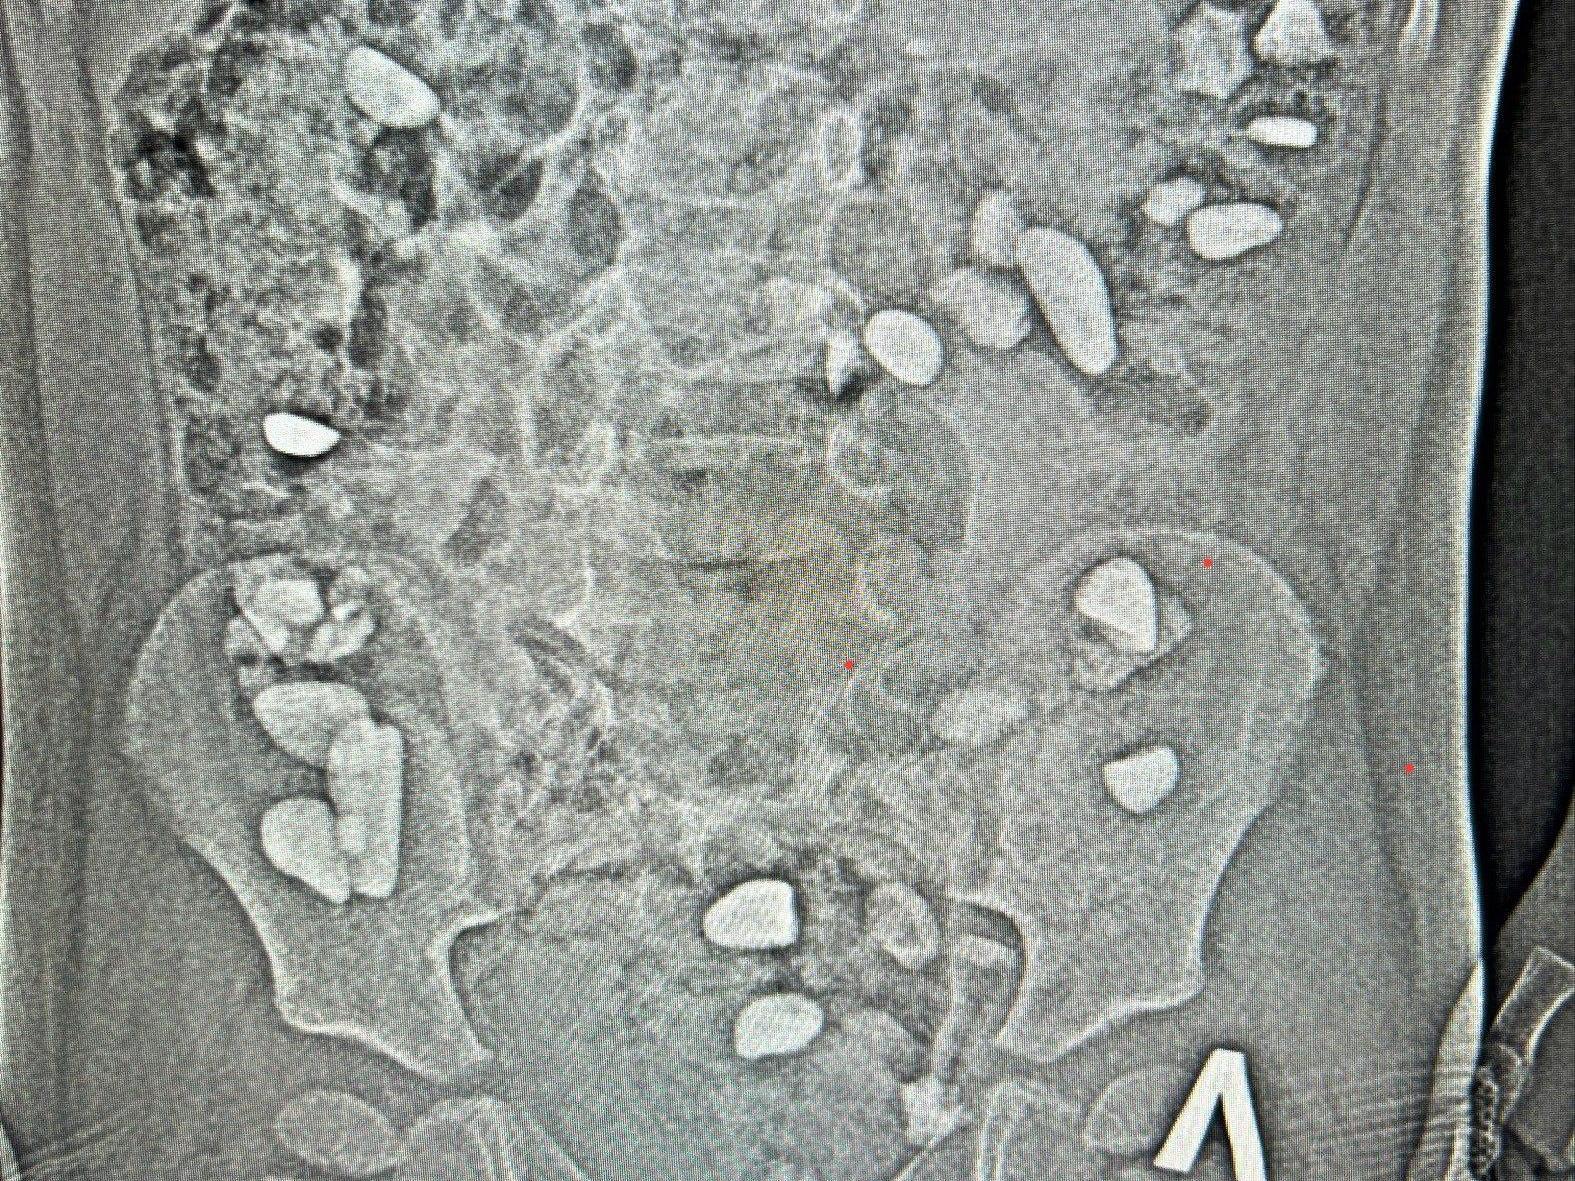

As reported by the medical facility, a pediatric surgeon ordered an X-ray, and in the image, doctors saw something no one expected: dozens of small foreign bodies were located in the projection of the colon. It was later discovered that the child had swallowed more than 25 stones. The boy«s parents could not explain when exactly this happened. Medical staff suggest that the toddler might have done this during a walk or while playing outside.

Doctors prescribed a course of cleansing and anti-inflammatory therapy and monitored the child«s condition for five days.

Fortunately, surgical intervention was not required: all the stones passed naturally, and the boy«s condition significantly improved.